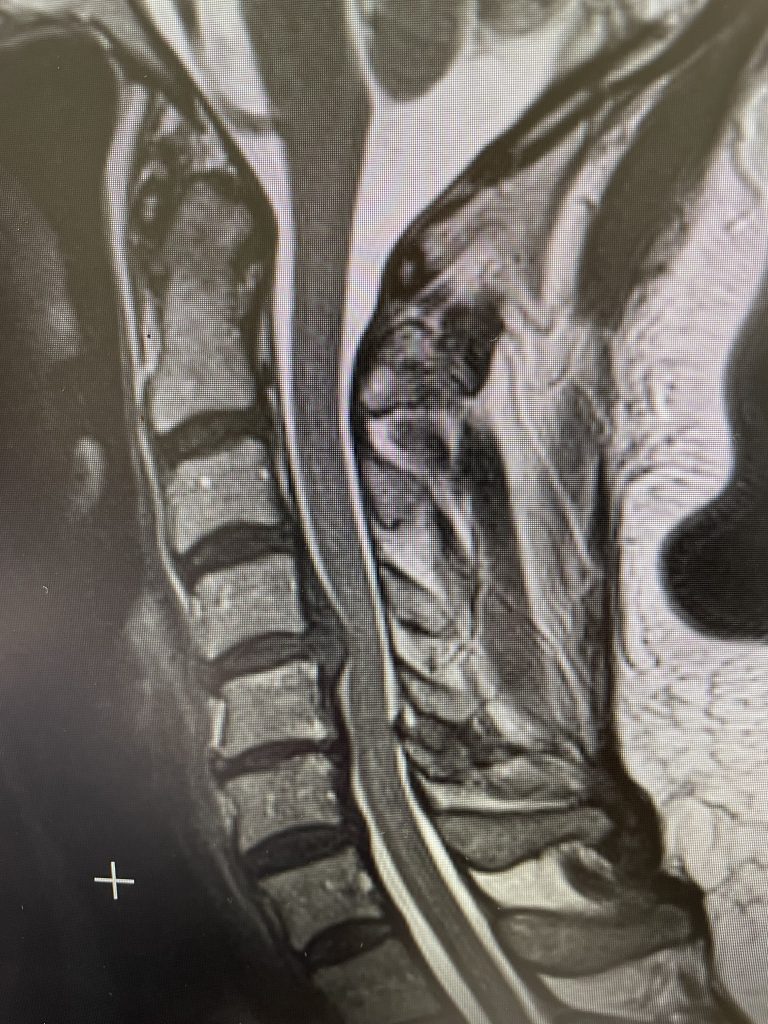

This 52 year-old female presents with 4 months of progressive neck pain, numbness of both hands, and difficulty using her hands and buttoning a shirt. She was noted to have mild right-sided weakness in a long track distribution which included her finger extensor, hip flexor, dorsiflexor weakness. She had tried chiropractic care. Imaging revealed a very large C4-5 disc herniation with severe cord compression which was more eccentric to the right, but also causing left-sided compression (Fig 1). The patient also had C5-6 disc collapse with biomechanical reduction of the C5-6 motion segment which puts more stress on the next segment. In essence the C5-6 is acting like it is autofused. This resulted in premature degeneration of the C4-5 segment which resulted in the disc herniation. It was decided, given a diagnosis of early cervical myelopathy with spinal cord compression, to offer an anterior cervical discectomy and fusion at C4-5 to decompress the spinal cord.